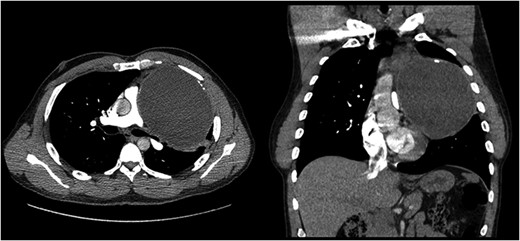

A CT scan of the chest (Fig. 1) revealed a 14 cm anterior mediastinal mass with both cystic and solid components, as well as compression of the pulmonary trunk, right main pulmonary artery and left main bronchus. Serum markers for alpha-fetoprotein and beta-human chorionic gonadotropin, to evaluate for germ cell tumor, were negative.

Computed tomography of the mediastinal mass. Transverse cross sectional view. The cystic mass is compressing the pulmonary trunk and the left main bronchus.